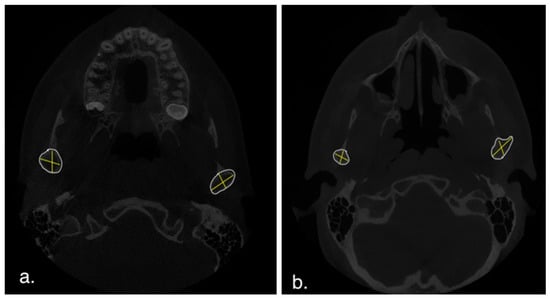

2.4.4. D Quantitative Assessment

3.3. D Quantitative Assessment